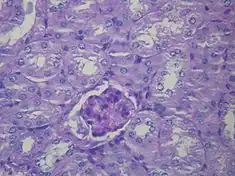

![]() Fotografía microscópica de un glomérulo lesionado consecuencia de una nefropatía diabética, la principal causa del síndrome nefrótico en adultos. | ||